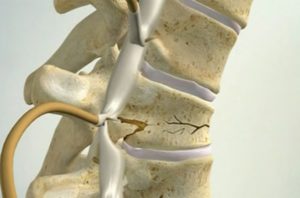

При компрессионном переломе позвоночник сильно сдавливается. Посредством большого давления позвонок приобретает клиновидную форму. Верхняя часть начинает выходить за «нормальные» границы, а углы начинают вдавливаться в нижний позвонок, структура которого начинает разрушаться.

Кстати. Механизм получения компрессионной травмы следующий – переломленным оказывается его позвонковое тело. Осложнение кроется в том, что поврежденный фрагмент может сдвинуться в сторону позвоночного канала и зажать находящийся там мозг.